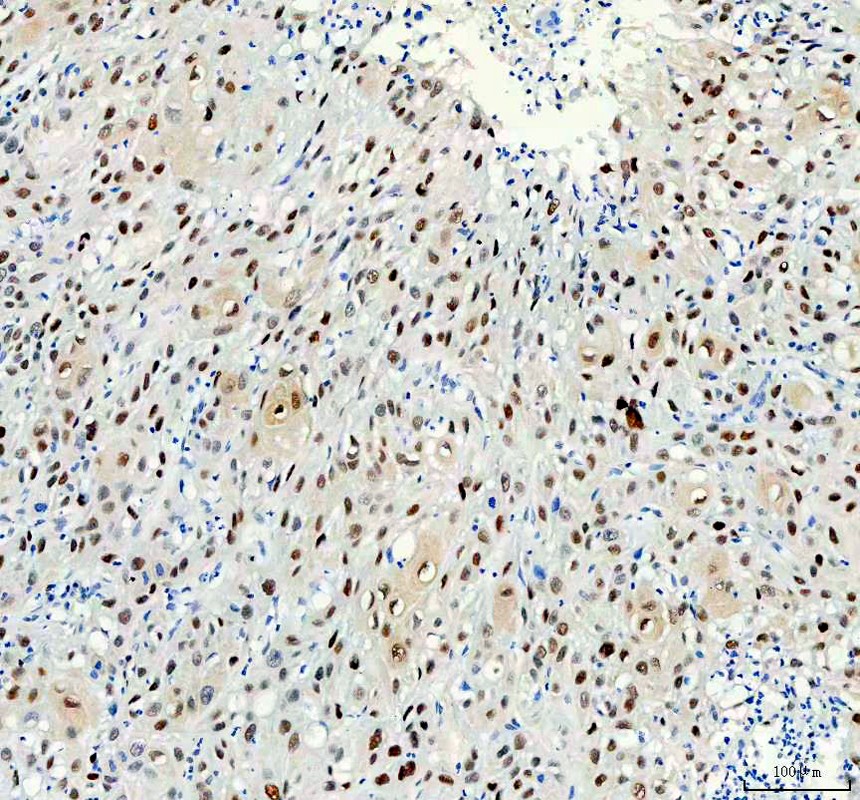

IHC analysis of P27/KIP1/CDKN1B using anti-P27/KIP1/CDKN1B antibody (BM4229) .

P27/KIP1/CDKN1B was detected in a paraffin-embedded section of human urothelial carcinoma with squamous differentiation tissue. The tissue section was incubated with rabbit anti-P27/KIP1/CDKN1B Antibody (BM4229) at a dilution of 1:200 and developed using HRP Conjugated Rabbit IgG Super Vision Assay Kit (Catalog # SV0002) with DAB (Catalog # AR1027) as the chromogen.